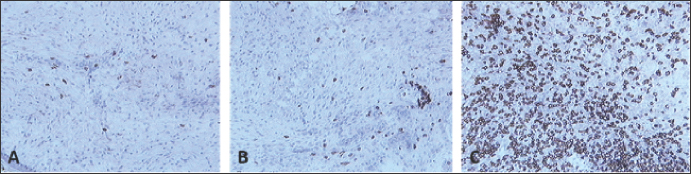

Fig. 2. Skin sections of birds vaccinated with FP9 and stained with monoclonal antibody DF6 against FPV. (A) 2 dpv, (B) 4 dpv, and (C) 6 dpv. Positive stained cells (cells infected with the FPV) appeared brown (100x magnification).

Skin sections from the site of vaccination were stained using a specific monoclonal antibody (DF6) against FPV (Boulanger et al., 2002).

FP9 was detected at two dpv and to a lower degree at 4 dpv. No virus was detected from 6 dpv onwards (Fig. 2).